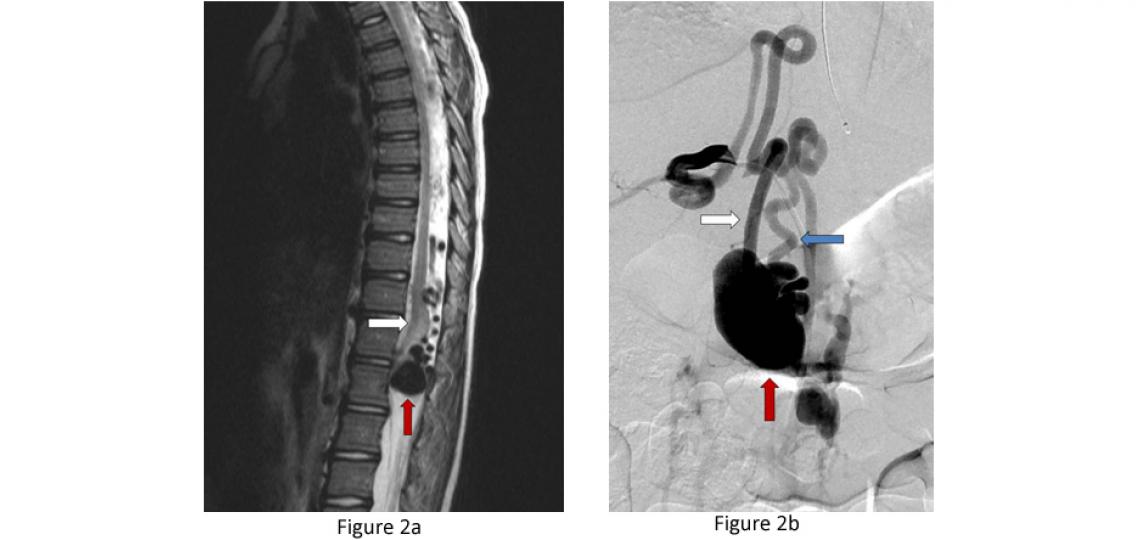

Pial Spinal Arteriovenous Fistulas (Type IV) - Pial AVFs refer to an abnormal connection between an artery and a vein on the surface of the spinal cord. They often come to attention when the vein has enlarged over time due to high pressure from the artery and begins to compress the spinal cord (Figure 2). These are rare lesions.

Figure 2a: Type IV pial spinal arteriovenous fistula – side view or sagittal T2 MRI of the spine showing a massively enlarged spinal vein (red arrow) compressing the spinal cord (white arrow). Figure 2b: A spinal angiogram of the same fistula demonstrating the enlarged artery (white arrow) connecting with the massively enlarged spinal vein (red arrow) and draining vein (blue arrow) leading out of the spinal canal.